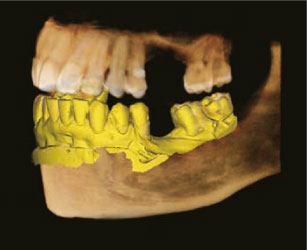

5 лицензии ПО Ez3D-i Endo - Программа для расширенной 3D-диагностики и планирования лечения, включающая в себя:

- программу для 3D-диагностики, планирования виртуального удаления, имплантации, реставрации зубов, диагностики ВНЧС, измерения объема дыхательных путей, консультации и формирования отчетов;

- программу Viewer для просмотра сохраненных данных с возможностью экспорта.Расширенный набор инструментов включает в себя:

- вкладка Ortho для моделирования перемещения элементов зубочелюстной системы с целью нормализации прикуса и устранения диспропорции лица; вкладка Segment для автоматического 3D-сегментирования костей и зубов с возможностью экспорта в виде отдельных файлов STL;

- вкладка Endo с новыми инструментами для планирования лечения каналов зубов: измерения кривизны каналов, вычисления поперечного сечения, визуализации каналов, сегментирования зубов для лучшего понимания анатомического и функционального строения зуба.